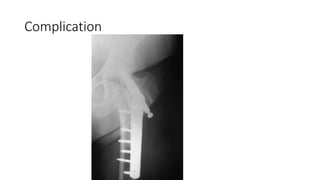

Complication

•